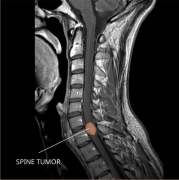

良性脊髓肿瘤的手术治疗:顺利

脊髓肿瘤是发生在脊髓内或脊髓附近的异常组织块。它们可以是...